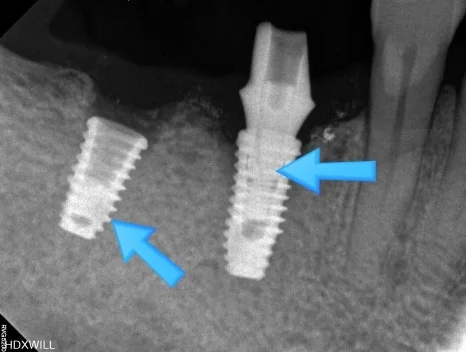

오산 임플란트 흔들림 계속 풀리는 경우에는 안녕하세요. 서울버팀치과 원장 엄용국입니다. 임플란트가 흔들리는 느낌이 들거나 나사가 느슨해지는 경우가 있습니다. 임플란트 보철물은 잇몸뼈 속에 심어져 있는 고정 나사와 연결되어 지탱되는 구조인데요. 그래서...